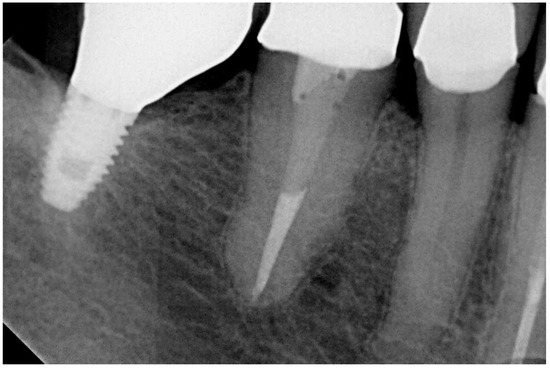

In the present study, short implants measuring 7 mm in length were used. In total, 217 short implants (NobelSpeedy Shorty, Nobel Biocare AB) were placed (21 in the maxilla and 196 in the mandible), out of the total of 157 rehabilitations (20 in the maxilla and 137 in the mandible), with 141 single teeth (16 in the maxilla and 125 in the mandible) and 16 partially fixed prostheses (4 in the maxilla and 12 in the mandible). A case illustration is presented in Figure 3, Figure 4 and Figure 5.

Figure 3. Follow-up periapical radiograph after the insertion of the short implant (4th quadrant).

Figure 4. Follow-up periapical radiograph illustrative of the 5-year follow-up of the short implant (4th quadrant).